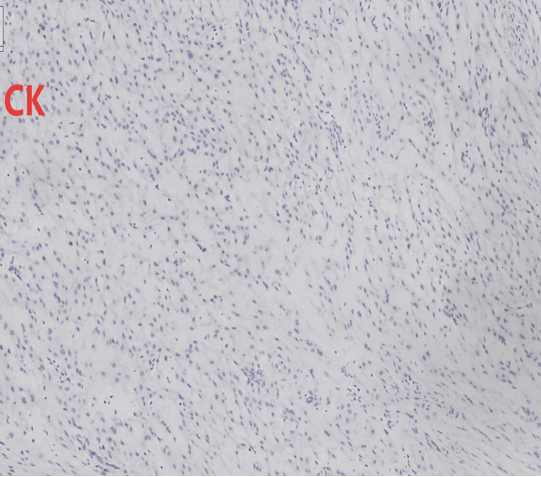

免疫组化结果:CK7(-)、CK5/6(-)、P63(-)、PAX-8(-)、Ki-67(+,约2%+)、INI-1(+,未突变)、SMA(+)、Des(+)、CD34(-)、S-100(-)、ER(+)、CK(-)、ALK(-)

(阴道前壁包块):上皮样平滑肌瘤伴黏液变性,富于细胞性,请结合临床并密切随诊。